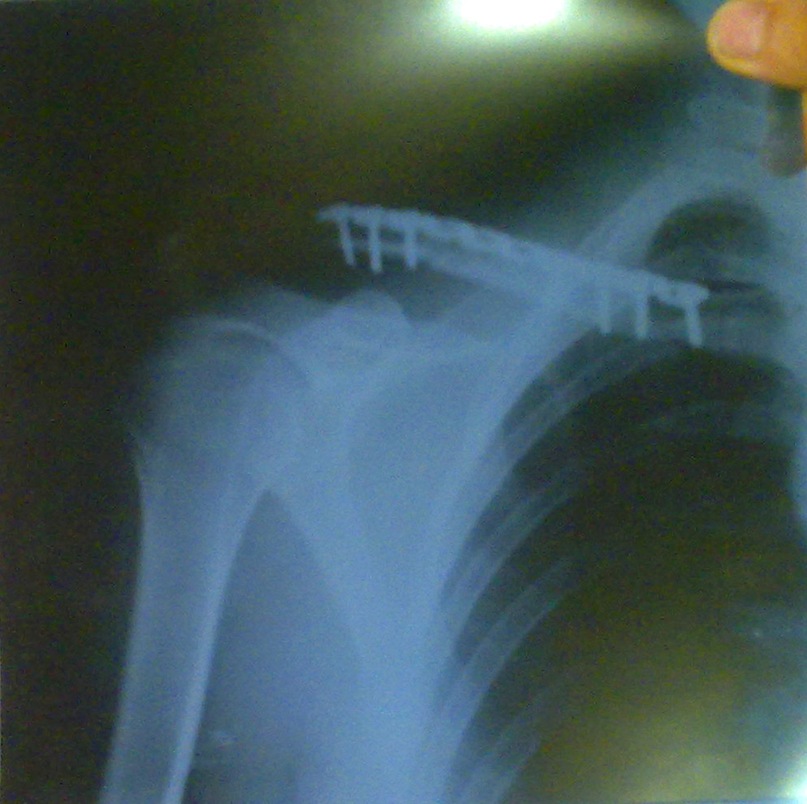

hlu386 \$m[1]:При переломе ключицы спица как раз используется для фиксации костей.

ему спицу собираются вставлять!!! один местный парень сейчас сказал что от новороссийских хирургов бежать надо, врачи дерьмовые! может там и операция не обязательна, а они собрались спицу в плечо втыкать!

musya747 \$m[1]:третий день в больнице, и до сих пор ему ничего не вправили..! это так и должно быть или это новороссийские врачи так работают?!